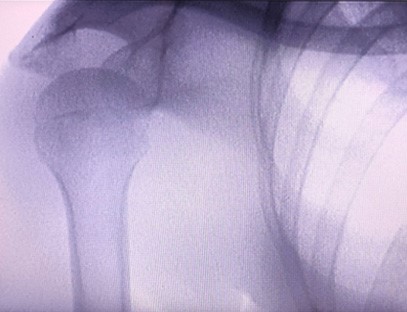

Ixtisosligi:Ortopediya klinikalari ehtiyojlari uchun mo'ljallangan, ayniqsa mos keladiRentgen tasviriqo'llar, bilaklar, tirsaklar, yelkalar, tizzalar, to'piqlar va boshqalar kabi a'zolarning.

Aniq tasvir:Yuqori sifatli rentgen tasvirlarini taqdim etish uchun ilg'or raqamli tasvirlash texnologiyasi qo'llaniladi, bu shifokorlarga kasallikni aniq tashxislashda yordam beradi.